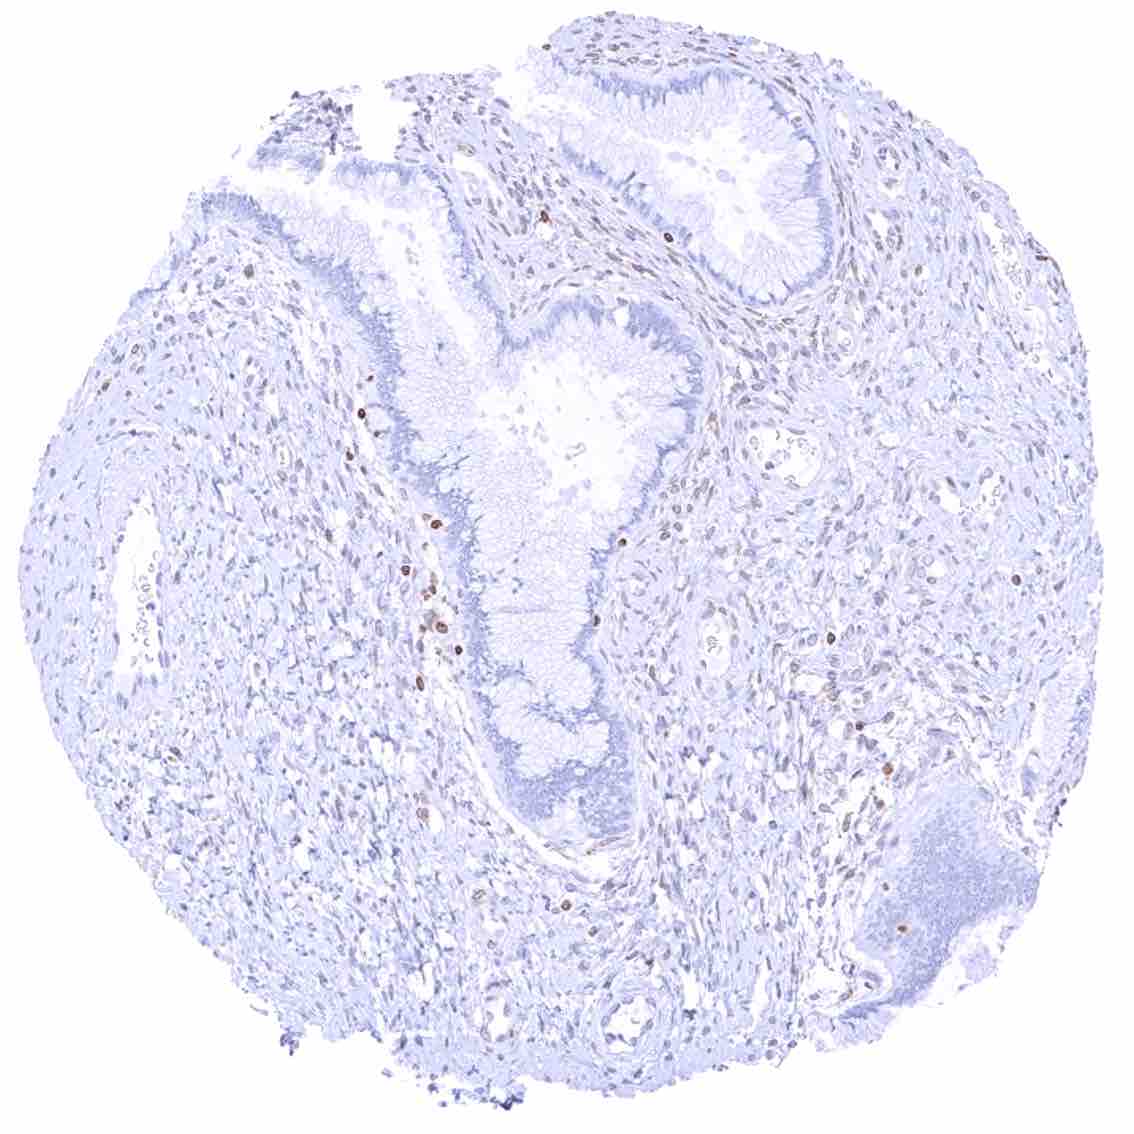

Prostate – Weak to moderate bcl-2 staining of a fraction of basal cells.